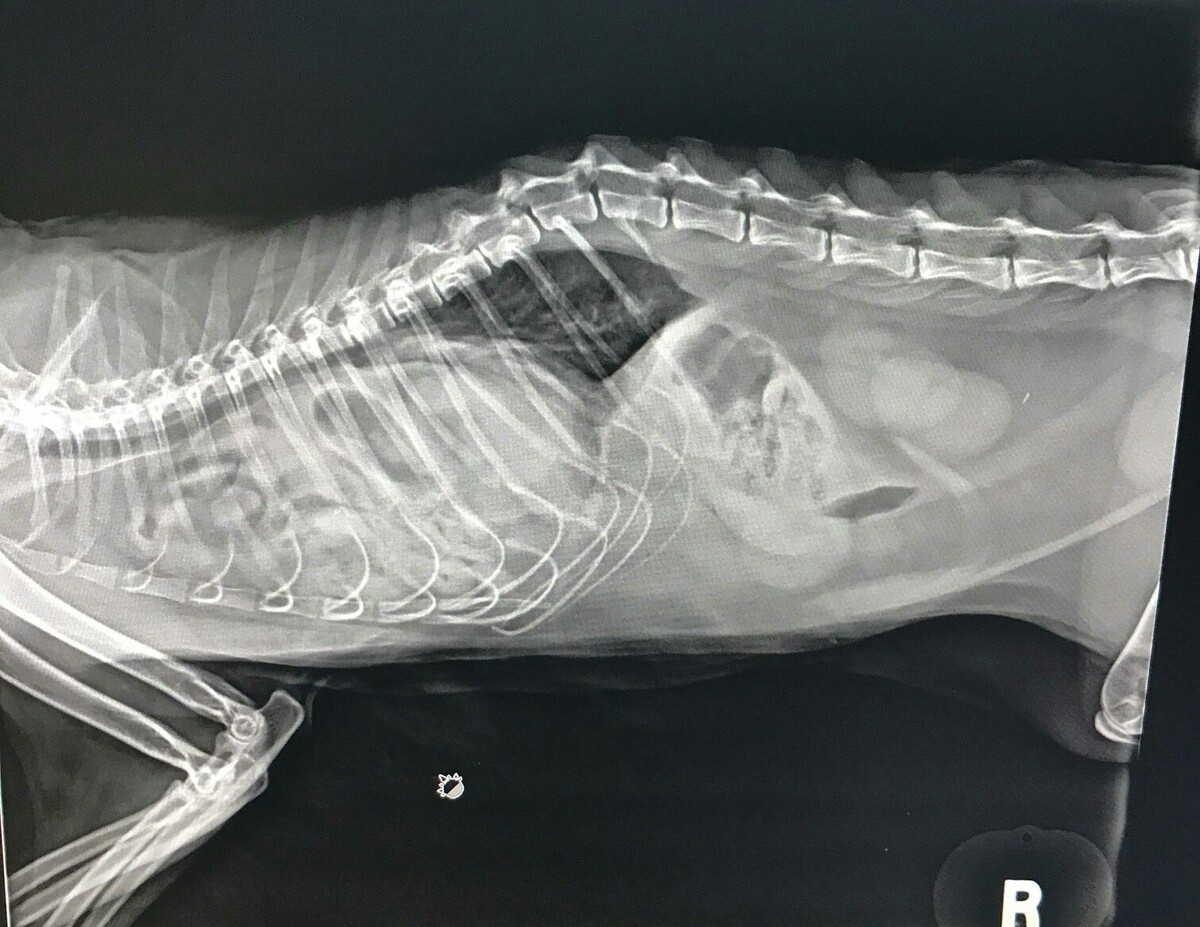

Это НЕ рентген нашего пациента, а наглядный пример диафрагмальной грыжи, с выпадением кишечника в грудную полость.